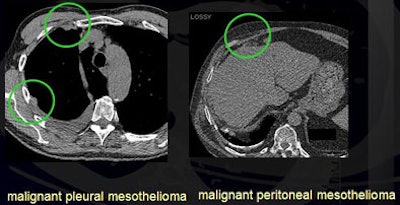

In addition, the researchers found two malignant pleural mesotheliomas and one malignant peritoneal mesothelioma, for an overall malignancy rate of 1.4% to 1.9%.

![]() |

| Detected malignancies included malignant pleural mesothelioma and malignant peritoneal mesothelioma. |